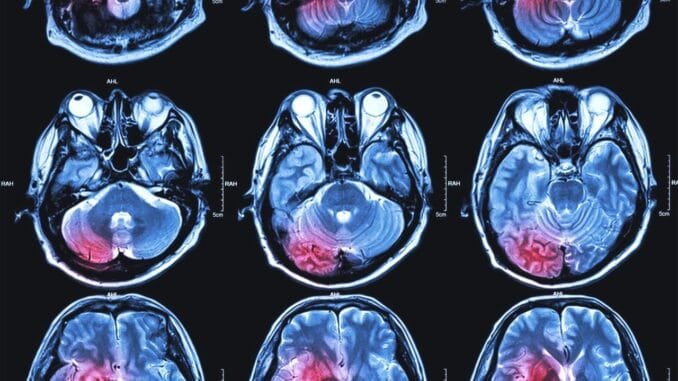

Michigan Üniversitesi bilim insanları, Proceedings of the National Academy of Sciences dergisinde yayımladıkları ilginç bir çalışmada, ölmekte olan bireylerin beyinlerinde gözlemlenen bilinmeyen ve gizemli bir beyin aktivitesi dalgasını nasıl tespit ettiklerini ayrıntılı bir şekilde açıkladılar.

Bu çalışma, geçtiğimiz yıl yaşam desteği altında olan bir hastanın beyin dalgalarını kaydeden önceki araştırmalarda tanımlanan kısa ömürlü gama aktivite patlaması ile benzerlik gösteren bir etkinlik olarak kaydedildi. Yapılan keşif, insan beyninin trajik koşullar altında nasıl tepki verdiğine dair daha fazla bilgi edinme fırsatı sunuyor.

Dört hasta yaşam desteğinden çekildiğinde, gizemli beyin aktivitesi kaydedildi. Bu dört hastadan ikisinde gözlemlenen aktivite, bilim insanlarının ölmekte olan insan beyinleri ile daha önce üzerinde çalışılan fareler gibi hayvanların beyinleri arasındaki benzerlikleri daha iyi anlamalarına yardımcı olabilir. Beyin ölürken ortaya çıkan bu titreşimlerin, hayatın gözlerimizin önünden geçmesi gibi, genellikle “ölüme yakın deneyimler” olarak adlandırılan fenomenlerle ilişkili olabileceği düşünülmektedir.